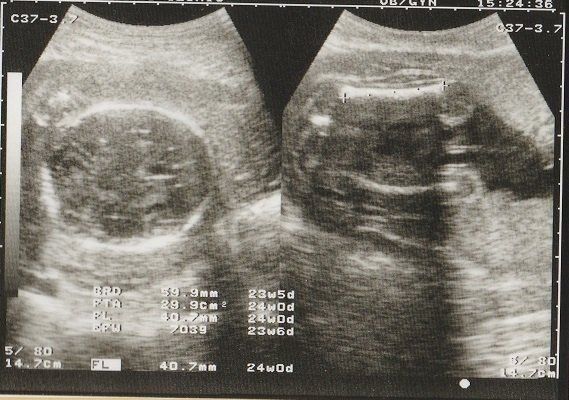

ママにエールさんの妊娠24週目のエコー写真

前回の妊婦検診から3週間後に出血して、この検診の前に慌てて受診したこともありました。原因は、“逆子”になっていた赤ちゃんに子宮を思い切り蹴られていたため。そんなこともありつつ迎えた、定期の妊婦検診。「出血はなくなりました」と先生に伝えたら、「赤ちゃんも逆子じゃなくなっているよ」と先生。ひとまず“逆子”がなおって良かったと主人にメールしました。